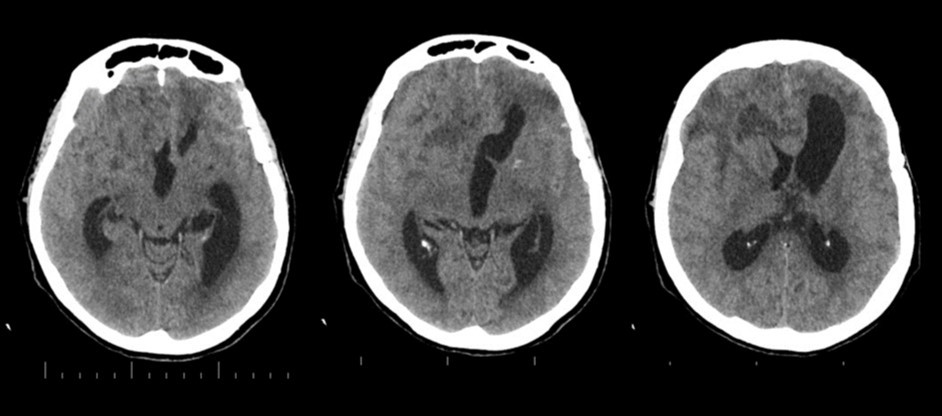

The follow-up CT scan made two weeks later showed a mild ventricular enlargement and persistent density alterations in the frontal region (Figure 2) that were interpreted as normal. Once discharged at home, the patient developed progressive disorientation that finally let her refer to our hospital for consult four months after aneurysm clipping. The cerebral CT we performed showed further ventricular growth, and a tumor-like image in the right frontal lobe (Figure 3). She was admitted to our ward and underwent a contrast-MRI that confirmed the suspicion of aggressive intra-axial neoplasm (Figure 4). The week after, under general anesthesia we performed a right craniotomy and removed a large part of the tumor, sparing the portion going through the corpus callosum (Figure 5). During convalescence the patient had few epileptic attacks, treated with drugs. A mild cognitive impairment persisted after surgery, without focal motor deficits. The gait, limited and unstable since the SAH, remained poor and the patient never walked again after the operation. The histological examination indicated a WHO grade IV glioma: IDH1-p53 negative glioblastoma. The patient and her relatives refused a ventriculo-peritoneal shunt after knowing this unfortunate diagnosis. Transferred to rehabilitation, the woman made just a short low-dose chemotherapy cycle and finally died four months after tumor resection.

Figure 3.4 months non-contrast CT scan. Ventricles are dilated. A mass clearly affects the right frontal and midline region

The clinical and radiological features of these two diseases are perfectly known to neurosurgeons; anyhow our case shows that trouble rises when they do occur simultaneously. The patient we described had initially acute signs due to SAH and later signs that were incorrectly interpreted as SAH-related. The tumor was almost invisible -because of its likely small volume and thick SAH- in the first CT performed (Figure 1). Analyzing the early follow-up CT (Figure 2) anyway things do not seem so clear. In the frontal region remained too much fogging close to the midline; the asymmetric distribution of such alteration should had point out a problem, but everybody kept thinking to a “simple” post-hemorrhagic condition, due to ventricular enlargement and focal ischemia. The initial mental impairment of that period was equally attributed to a normal SAH result with moderate hydrocephalus. The proper diagnosis of glioma happened late, and the patient was at that point unable to have significant benefits from surgery.